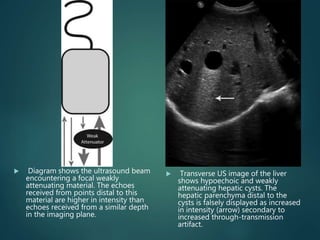

 Diagram shows the ultrasound beam

encountering a strongly attenuating

material. The echoes received from

points distal to this material are

significantly lower in intensity than

echoes received from a similar depth.

encountering a focal weakly

attenuating material. The echoes

received from points distal to this

material are higher in intensity than

echoes received from a similar depth

in the imaging plane.

 Transverse US image of the liver

shows hypoechoic and weakly

attenuating hepatic cysts. The

hepatic parenchyma distal to the

cysts is falsely displayed as increased

in intensity (arrow) secondary to

increased through-transmission

artifact.